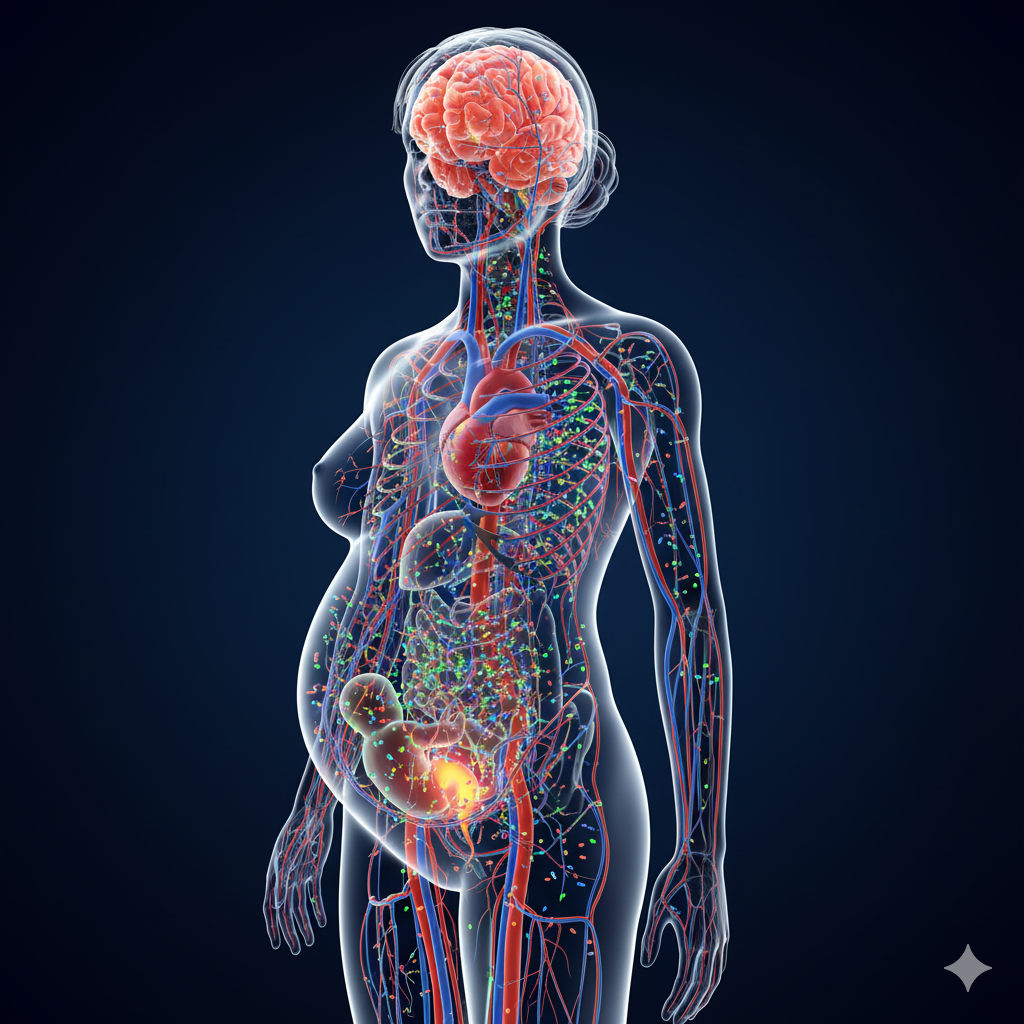

- Im menschlichen Körper: Eine wegweisende Studie fand in 17 von 22 Probanden Mikroplastik im Blut. Noch alarmierender ist eine Studie von Februar 2024, die in allen 62 untersuchten menschlichen Plazenten Mikroplastik nachwies, hauptsächlich Polyethylen (54%). Dies beweist die Überschreitung der ultimativen biologischen Barriere.

Diese chemische Flut bleibt nicht “draußen” in der Umwelt. Sie landet direkt in uns – mit messbaren und alarmierenden Folgen.

Unser Körper ist zur letzten Senke für diese langlebigen Chemikalien geworden.

- Nachweis im Blut und in Organen: Studien der US-Gesundheitsbehörde CDC zeigen, dass praktisch die gesamte Bevölkerung der USA “ewige Chemikalien” wie PFAS im Blut hat. Mikroplastik wurde sogar in den Plaques von verengten Halsschlagadern nachgewiesen. Eine Studie im New England Journal of Medicine fand bei über 50 % der untersuchten Patienten Mikro- oder Nanoplastik in diesen Arterien und verband deren Vorhandensein mit einem 4,5-fach höheren Risiko für Herzinfarkt, Schlaganfall oder Tod innerhalb der folgenden Jahre.

- Endokrine Disruptoren (EDCs): Ein besonders beunruhigendes Beispiel sind hormonell wirksame Substanzen, die in vielen Pestiziden, Weichmachern oder Kunststoffen enthalten sind. Sie können bereits in winzigen Dosen unser empfindliches Hormonsystem kapern und fehlsteuern. Ein wegweisender Bericht der WHO und des UN-Umweltprogramms listet wissenschaftlich belegte Assoziationen mit einer Reihe von Krankheiten auf: von Unfruchtbarkeit und Geburtsfehlern über Entwicklungsstörungen bei Kindern (z.B. ADHS, Autismus) bis hin zu einem erhöhten Risiko für hormonabhängige Krebsarten (Brust-, Prostata-, Schilddrüsenkrebs).

- Pränatale Belastung: Das vielleicht Schockierendste ist, dass die chemische Belastung bereits vor der Geburt beginnt. Viele dieser Chemikalien überwinden die Plazenta-Schranke und werden direkt an ungeborene Babys weitergegeben. Die bereits erwähnte Studie, die in jeder einzelnen von 62 untersuchten menschlichen Plazenten Mikroplastik fand, beweist, dass der Fötus direkt den Plastikpartikeln und den daran anhaftenden Chemikalien ausgesetzt ist, während sich seine Organe entwickeln. Die “Baseline” der chemischen Belastung für eine neue Generation liegt nicht mehr bei Null.